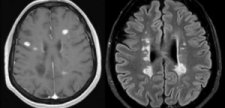

Reunión de Consenso Radiológico en el Diagnóstico y Seguimiento de la Esclerosis Múltiple

El próximo día 10 de Febrero de 2017 tendrá lugar en el Hospital Universitari i Politènic la Fe de Valencia (Aula H009) una reunión de Neurología y Radiología sobre Consenso radiológico en diagnóstico y seguimiento de la Esclerosis Múltiple, organizada por los Dres. Ventura Casanova y Luis Martí Bonmatí.